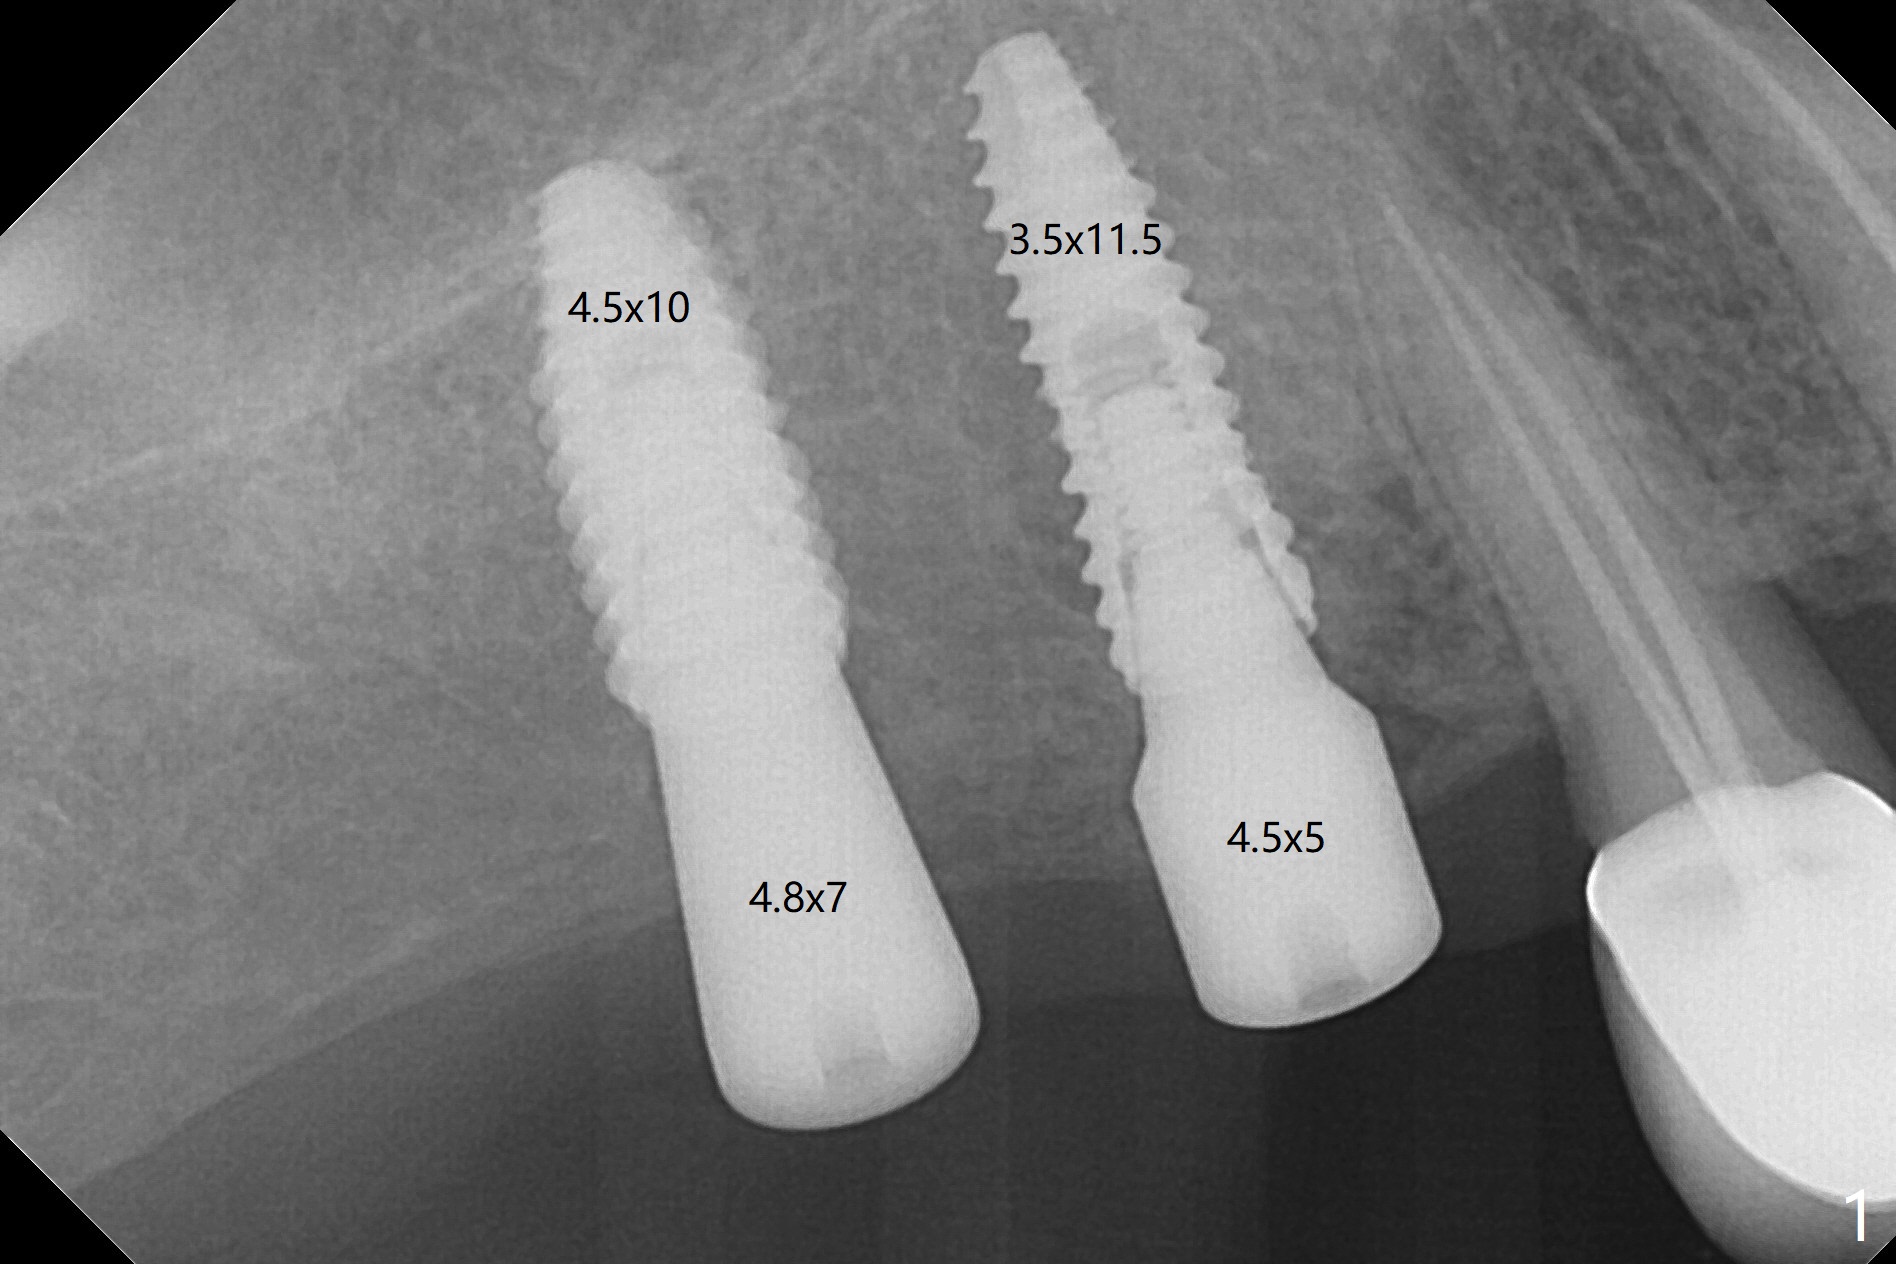

There is history of mild postop hemorrhage for a few days postop, as related to healing laceration palatal to #4 (7 days postop, Fig.2).  There is mild discomfort when temporary splinted crowns are fabricated 2.5 months postop (Fig.3).